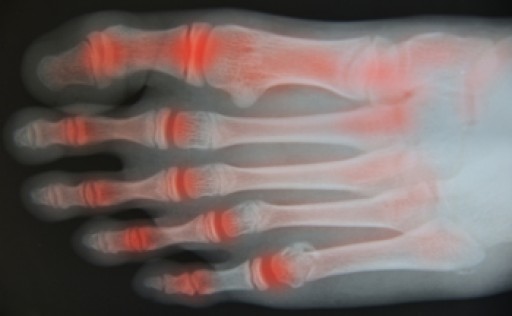

Arthritis: What Causes It & How to Treat It

Arthritis occurs when the cartilage that lines the body’s joints becomes inflamed. This inflammation can lead to swelling, redness, warmth and pain. Because each foot has 33 joints that can be affected by arthritis, it is a common cause of foot pain. Arthritis comes in a variety of forms, including osteoarthritis, gout and rheumatoid arthritis. While heredity plays a role in developing arthritis, infections, drugs, and trauma can all lead to this condition as well. Those who are suffering from arthritis in their feet should seek the care of a podiatrist for treatment. Nonsurgical treatment options that focus on providing comfort include wearing proper footwear with a wide toe box, orthotics with extra cushioning, and forefoot supports.

Arthritis is a term that is commonly used to describe joint pain.  The condition itself can occur to anyone of any age, race, or gender, and there are over 100 types of it.  Nevertheless, arthritis is more commonly found in women compared to men, and it is also more prevalent in those who are overweight. The causes of arthritis vary depending on which type of arthritis you have. Osteoarthritis for example, is often caused by injury, while rheumatoid arthritis is caused by a misdirected immune system.